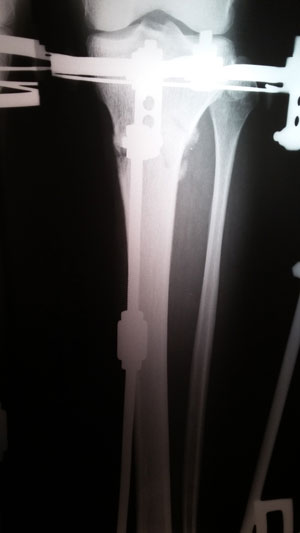

Рентген в 60 дней.

Здравствуйте, Viktorija! регенерат идёт хорошо, но будем выжидать 3 месяца (в 90 дней ждём рентген).